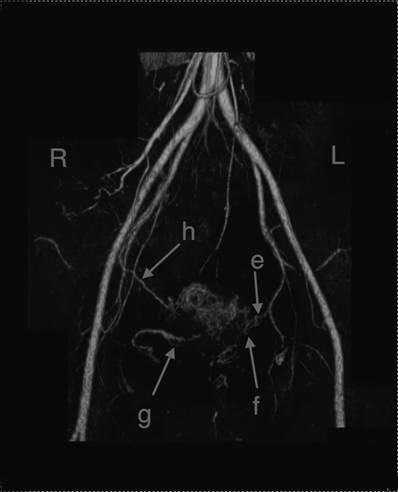

Figures 1 and 2 show the blood vessel distribution in the uterus for both patients. Figure 3 shows the blood distribution in the normal uterus after the delivery. Identification of blood vessels was performed by a radiologist (M.T).

Fig 2

3-D CT imaging of patient 2. e: Left uterine artery. No descending branch was seen. f: New vessels probably arisen from ascending branch of left uterine artery and some arteries from vagina or pelvic wall . g: New vessels probably arisen from some arteries from vagina or pelvic wall. h: Right ovarian artery supplying blood to the remaining uterus. No right uterine artery could be detected. Main blood supply of the right side of the uterus was through “g” and “h”. Identification of each vessel was also made by a radiologist (M.T).

In vaginal RT, we usually amputate the cervix at the level of the uterine artery, which corresponds to approximately 10 mm below the isthmus. In this procedure, we usually ligate and cut the descending branches of the uterine arteries and vaginal arteries. These arteries mainly supply blood to the lower segment of the uterus. Fig. 1 and Fig. 2 show that the descending branches of uterine arteries and vaginal arteries could not be seen in either patient. New arterial vascularization from the ascending branches of uterine arteries arose, and these new vessels seemed to supply blood to the remaining cervix, including the neo-cervix. On the 3-D CT scan, no ischemic areas were seen in the remaining uterus.